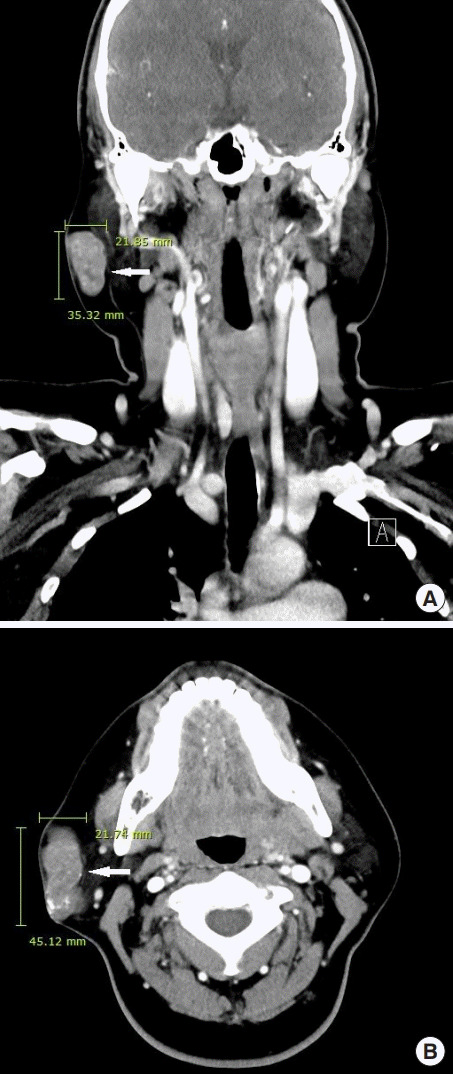

進(jìn)行超聲檢查以確定腫塊是否為腮腺腫瘤,并顯示與腮腺分離的異質(zhì)腫塊(圖 2)。 進(jìn)行了頸部對比增強(qiáng)計(jì)算機(jī)斷層掃描和超聲引導(dǎo)穿刺活檢。 在右下頜角,它表現(xiàn)為邊界清楚、分葉狀和不均勻強(qiáng)化的腫瘤,在皮下脂肪層和淺表肌肉腱膜系統(tǒng)中有鈣化部分(圖 3)。 穿孔活檢顯示與毛母質(zhì)瘤一致的特征,并且在超聲引導(dǎo)下對頸部淋巴結(jié)進(jìn)行抽吸活檢時(shí)未發(fā)現(xiàn)腫瘤細(xì)胞。

圖 3:頸部對比增強(qiáng)計(jì)算機(jī)斷層掃描的冠狀 (A) 和軸位 (B) 視圖顯示右腮腺區(qū)域(箭頭)中邊界清楚、分葉狀、不均勻的病變。